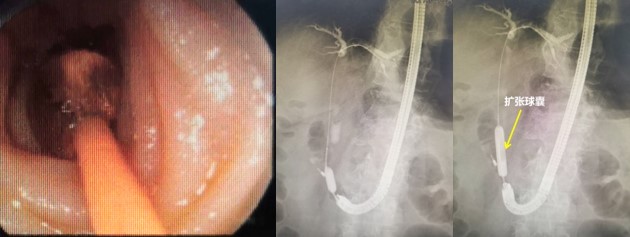

赵刚副主任凭借丰富的经验和精湛的技术,运用胃镜佩戴透明帽顺利找到前期设定的钛夹标记及十二指肠主乳头,然后利用专业器械,在内镜精细操作下,成功进行乳头括约肌切开及球囊扩张术,并最终将胆管内结石顺利取出。整个操作用时不到20分钟。

毕Ⅱ式胃大部切除术后的ERCP操作难度比普通ERCP超出很多,首先就是内镜的选择,按照《中国ERCP指南(2018版)》的建议,推荐首选十二指肠镜进行操作,但十二指肠镜在进镜操作以及寻找输入袢和十二指肠乳头方面明显不如直视镜。消化内科团队通过前期数年来的工作积累,制定了毕Ⅱ式胃大部切除术后ERCP操作的“交大二附院流程”,那就是先进行胃镜检查,由操作者亲自确认术式、输入袢肠管的走行以及十二指肠主乳头的位置,同时在内镜下对乳头进行定位标记,另外,对于输入袢开口较为隐蔽或内镜通过输入袢口较为困难的病例,操作者也会在输入袢口处额外进行标记,以便于后续ERCP操作时的二次寻找。在手术操作过程中,消化内科ERCP团队一般都会选用胃镜佩戴透明帽进行操作,透明帽一方面有利于进镜寻找目标肠袢,另一方面也可提高乳头插管时的镜身稳定性。